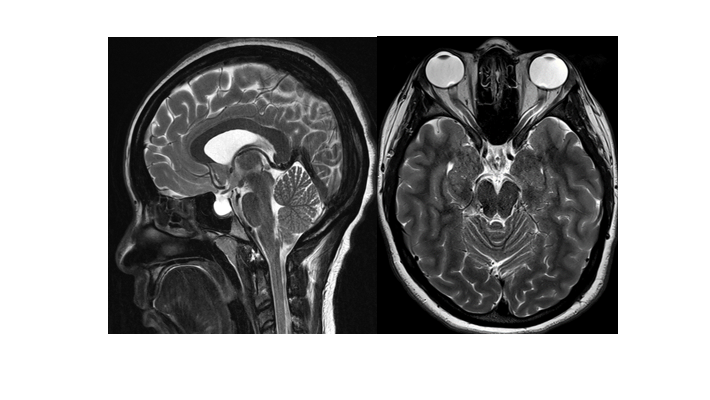

בתמונה: MRI בתסמונת פסאודוטומור צרברי

רופא העיניים חוקר את ההיסטוריה הרפואית של המטופל, בודק את העיניים, מאתר הבצקת בעצבי הראייה ומפנה לבדיקות הדמיה מוחיות (CT או MRI). מטרת ההדמיה היא לשלול תהליך תופס מקום או מחלה אחרת הגורמת לעלית הלחץ התוך גולגולתי. בהדמיה ייתכנו ממצאים נוספים המרמזים להימצאות לחץ תוך גולגולתי גבוה. בנוסף מבוצע ניקור מותני לגילוי לחץ הפתיחה המוגבר ושלילת מחלה אחרות בעזרת בדיקת הרכב הנוזל המוחי-שדרתי (CSF).